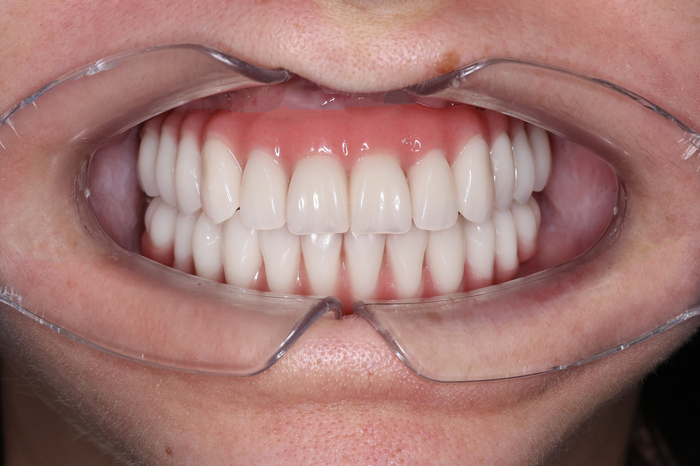

Результат: получили физиологический прикус, нормализовали смыкание фронтальной группы зубов во всех плоскостях (сагиттальной, вертикальной и трансверзальной). Добились правильного смыкания зубов в боковых отделах. Расширили зубные ряды и нормализовали наклон резцов верхней челюсти.

Мы осуществили большую мечту нашего пациента и подарили этому миру еще одну красивую и здоровую улыбку!

В конечном итоге пациент получил правильный прикус и красивую улыбку, не прибегая к операции на челюстях.